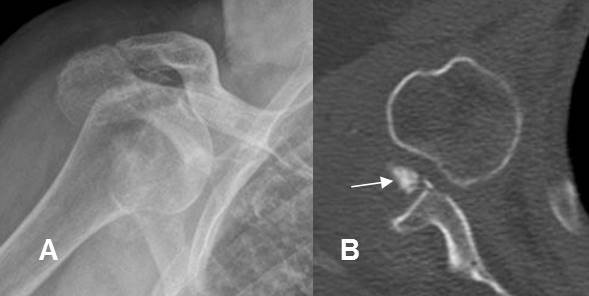

Fig 158. Luxación glenohumeral.

A: Rx AP. Luxación glenohumeral anterior.

B: TAC axial. Se confirma la luxación. Adicionalmente hay un fragmento libre intra-articular.